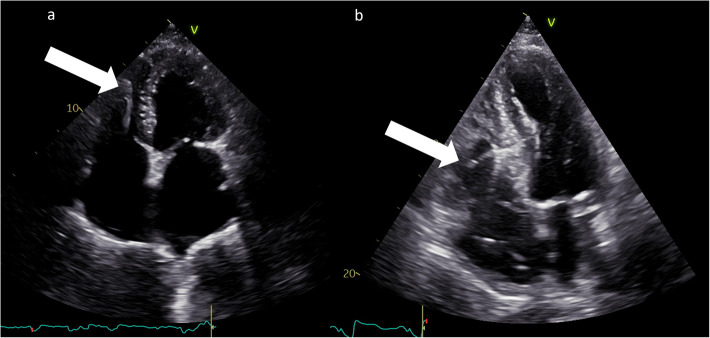

Conduction system pacing (CSP), encompassing His-bundle pacing (HBP) and left bundle branch area pacing (LBBAP), revolutionizes cardiac pacing, allowing a more physiological left ventricular activation than conventional right ventricular (RV) pacing through electrode placed in RV apex, interventricular septum or right ventricular outflow tract. Echocardiography plays a pivotal role in patient assessment, primarily by measuring left ventricular ejection fraction (LVEF) to determine the pacing strategy in alignment with current guidelines. Clinical data, simulations and ongoing trials on CSP explore CSP viability across various LVEF conditions. CSP is supposed to defer pacing-induced cardiomyopathy (PiCM) associated with conventional right ventricular pacing (RVP). This paper aims to review the current literature regarding the use of echocardiography in CSP. Images from our experience in the echocardiographic lab were used throughout this document to show our proposals of imaging in CSP. Echocardiography may help to determine lead localization within the interventricular septum (IVS), customizing pacing to individual anatomy and electromechanical indices (like atro-ventricular delay) and evaluates often-overlooked valvular function, a potential PiCM contributor. Three-dimensional (3-D) echocardiography widens the knowledge of lead localization and valvular dysfunction, as well as dyssynchrony assessment. Dyssynchrony, crucial both to resynchronization per se and physiological stimulation is quantified via echocardiography, especially using speckle-tracking imaging. Baseline LVEF and follow-up observation of CSP effects: early in Global Longitudinal Strain (GLS), afterwards in LV volumes and LVEF may improve the future proper qualification of patients. Limited left atrial (LA) and right atrial (RA) strain assessments hold potential in the CSP qualification and response assessment context. Echocardiography complements other imaging modalities for comprehensive patient evaluation. Echocardiography is integral in the CSP clinical use, from patient selection (by showing subtle changes in myocardial function) to post-procedure follow-up (tricuspid regurgitation, LV and RV function, leads and synchrony assessment). GLS, assessed by speckle tracking imaging and profound 2D and 3D (lead placement, septum morphology and global heart function under CSP) analyses show promise in CSP outcome assessment, though standardization is needed.